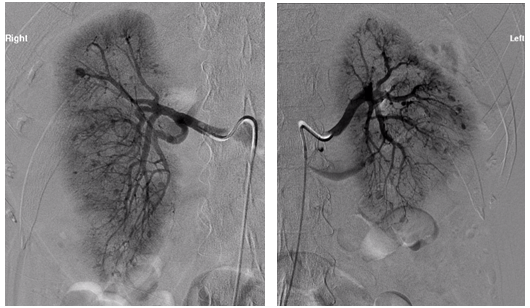

An unclear picture led to a CT pulmonary angiogram, which did not reveala pulmonary embolism but it was incidentally found that there were bilateral large renal haematomas (Figure 1). Subsequent blood tests revealed worsening renal function, inflammatory markers, and anaemia requiring blood transfusions. The patient was also found to be ANCA positive with a raised MPO titre of 134U/ml. A renal angiogram was performed and showed several renal artery aneurysms (Figure 2).

Figure 1 A) CT contrast abdomen, axial view showing bilateral capsular and subcapsular renal haematomas. B) CT abdomen sagittal view.